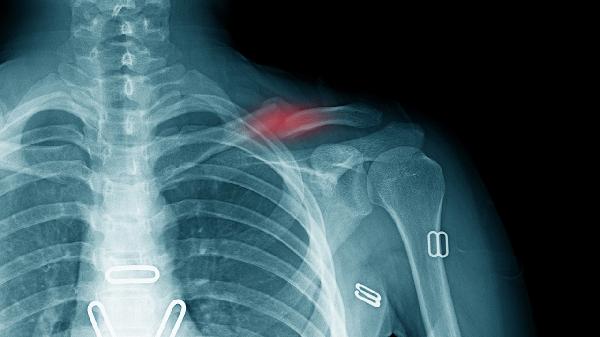

骨折治疗需遵医嘱综合管理,除药物治疗外应保证充足优质蛋白和钙质摄入,适当补充维生素D。康复期在医生指导下进行渐进式功能锻炼,避免过早负重。定期复查X线观察骨痂生长情况,出现异常疼痛或肿胀应及时就诊。注意保持患肢抬高,戒烟限酒以促进骨折愈合。